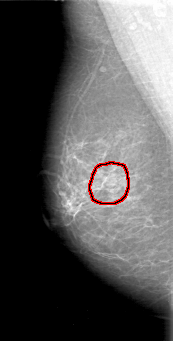

D_4027_1.LEFT_MLO

LEFT_MLO LINES 5386 PIXELS_PER_LINE 2746 BITS_PER_PIXEL 12 RESOLUTION 43.5 NON_OVERLAY

FILE: D_4027_1.RIGHT_CC.OVERLAY

TOTAL_ABNORMALITIES 1

ABNORMALITY 1

LESION_TYPE MASS SHAPE OVAL MARGINS OBSCURED

ASSESSMENT 0

SUBTLETY 3

PATHOLOGY BENIGN

TOTAL_OUTLINES 1

BOUNDARY